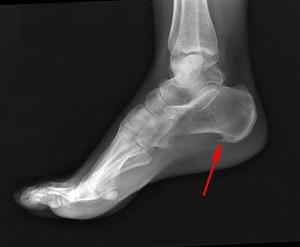

Название патологии выбрано не случайно — на рентгеновских снимках видно костное образование на пятке, напоминающее шпору.

На рентгеновских снимках четко видны изменения в структуре голеностопа, вызванные образованием шпоры, а ультразвуковое исследование выявляет воспалительный процесс в мягких тканях. При пальпации пациент ощущает сильную боль, сравнимую с ходьбой по осколкам стекла.